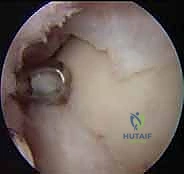

- التنظير التشخيصي للمفصل (Diagnostic Arthroscopy): في بعض الحالات المعقدة، يتم إدخال كاميرا دقيقة (منظار) داخل الكاحل لتقييم الغضروف بالرؤية المباشرة وتقييم مدى صلابته.

1. الاستكشاف والتنظيف: يُدخل الدكتور هطيف الكاميرا الدقيقة لتقييم حجم الآفة بدقة، وتنظيف أي أنسجة تالفة أو أجسام حرة داخل المفصل.

2. أخذ الخزعة (Biopsy): يتم أخذ عينة صغيرة جداً من الغضروف السليم (بحجم حبة العدس أو أقل من 200-300 مليغرام) من منطقة غير حاملة للوزن في المفصل (Non-weight bearing area)، بحيث لا يؤثر أخذها على وظيفة الكاحل.